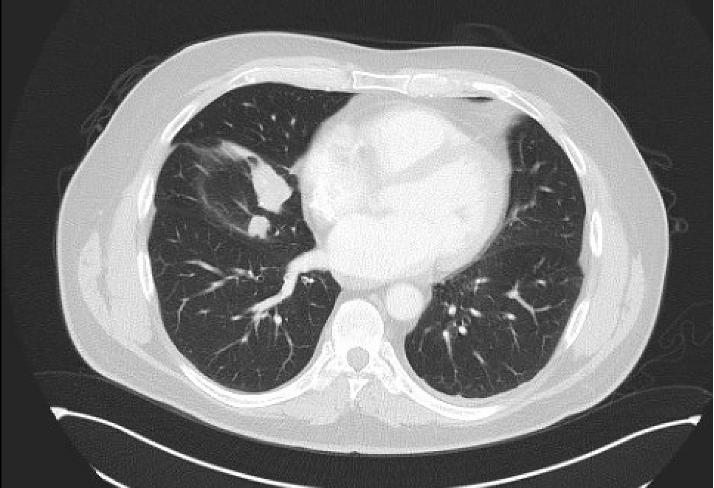

🩻mets to 🫁

🩻PD in 🫁

🩻PR after 6 mos

🩻 Scans: new 🫁 nodules